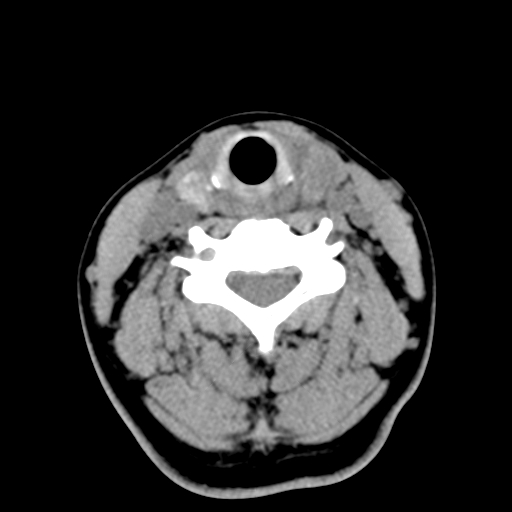

女,44岁,左颈部肿块伴疼痛两个月。患者不能做增强扫描。

左侧甲状腺明显肿大,密度不均匀性减低,正常之钙化基本消失,残留少许呈云雾状及颗粒状。其边缘不规则、不清晰,与前部联合处正常甲状腺不能分界不清,但尚可与周围其他组织分辨。颈动脉鞘区无明显淋巴结肿大。

多考虑:左侧甲状腺癌。

多考虑:左侧甲状腺占位,建议穿刺活检。

左侧甲状腺弥漫性肿大,密度减低,与气管及周围血管等分界清晰,颈部未见明显淋巴结肿大.首先考虑左侧甲状腺瘤;其次考虑甲状腺炎;不排除甲状腺癌可能.

多考虑甲壮腺腺瘤可能性大,周边的脂肪间隙显示尚清楚,未见明显肿大淋巴结.气管未见受压.